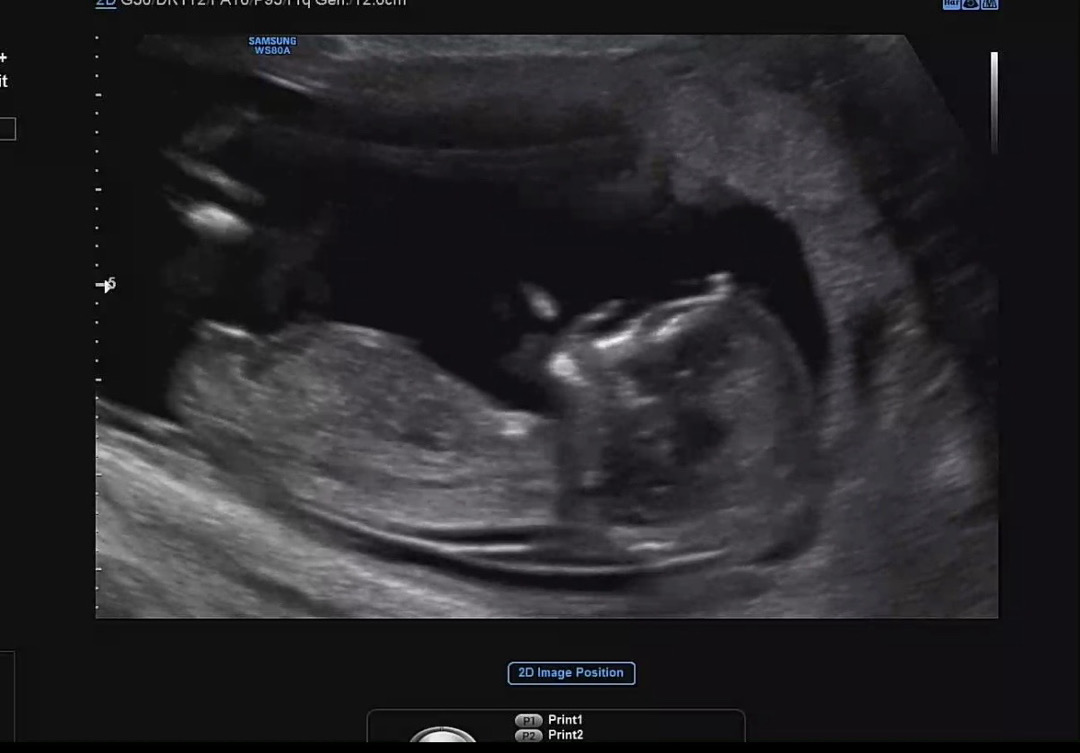

12์ฃผ ์ด์ํ์ธ๋ฐ ๊ถ๊ธํ๋ค์..? ์ด์ฐ๋ชจ๋ผ ์๋ฌด๊ฒ๋ ์์ธก ๋ชปํ๊ฒ ์ด์ ใ ใ ํฌํ ํ๋ฒ์ฉ ๋ถํ๋๋ ค์!!